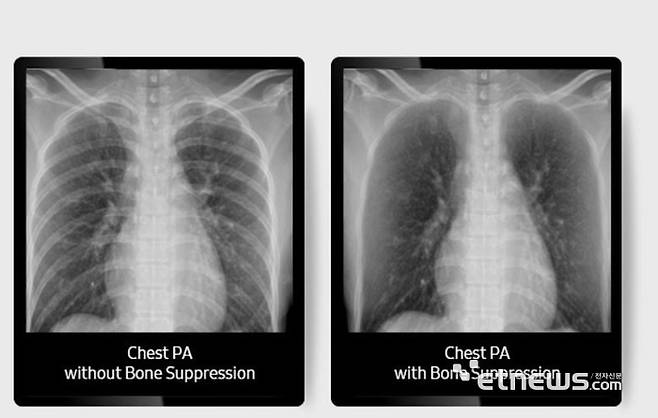

저선량 지원은 물론 최신 인공지능(AI) 기능도 탑재했다. 흉부 엑스레이 영상 판독을 지원하는 '루닛 인사이트 CXR' 솔루션을 탑재했으며, 주요 임상 구조물 화질을 높여주는 '심그리드', 폐 영역 연조직이나 병변 등 판독을 지원하는 '본 서프레션' 기능도 지원한다.